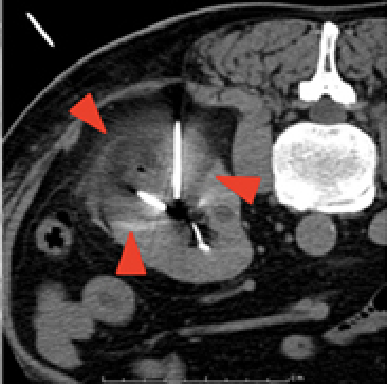

治療中

右腎臓の摘出後の患者さんで、左腎臓にがんができています。治療中では腫瘍が黒い部分で覆われており(赤い印で囲まれた範囲)、氷ができているのがわかります。治療後では腫瘍が壊死しているのがわかります。